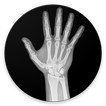

Easy age calculator using medical procedure called "bone age".

This application allows an experimented doctor evaluate by visual comparison of a radiography which is the age of a pediatric patient basing on the maturity status of his/her bones.